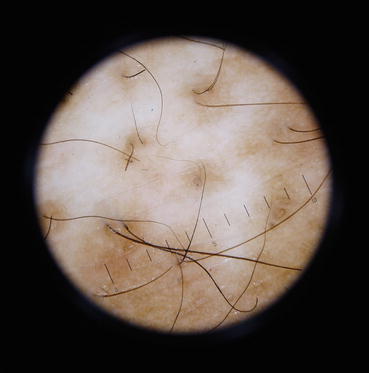

Fig. 22.3

Reversed pigmentary network in an early lesion of vitiligo

Reversed pigmentary network, a well-described finding in the dermoscopy of melanoma and melanocytic nevus, refers to a white or depigmented net-like pattern with pigmentation. It is similar to the salt and pepper pattern reported by Chandrashekar [2]. In vitiligo, there is a gradual loss of melanocytes and melanin which allows the light to directly pass into the dermis without being reflected by the melanocytes and melanin. This leads to a window through which light passes into the dermis and is reflected by dermal collagen.

In the initial stages of evolving vitiligo, this leads to an area of relative hyperpigmentation produced by the pale area corresponding to the papillary dermis in the normal reticulate pattern of pigmentation. The appearance of “reversed pigmentary network pattern” in evolving vitiligo is thus seen.